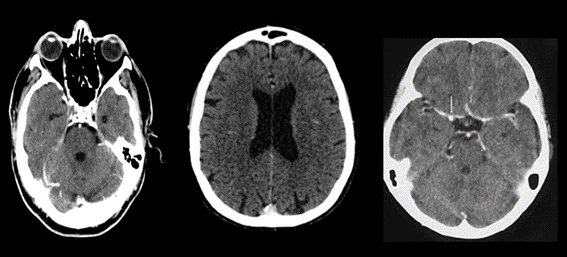

El primero de todos es la asimetría ventricular, caso en el que observamos a un ventrículo de mayor tamaño respecto al contralateral sin que esto signifique hidrocefalia. Esto lo podemos corroborar al identificar las astas temporales de similar tamaño.

Fig. 1.

El segundo error habitual puede producirse ante la presenta de una coartación ventricular. Esto consiste en un contacto de las paredes ependimarias sin valor patológico suele ser confudnido con lesiones con efecto de masa.

Fig. 2.

Las calcificaciones del sistema ventricular constituyen un error clásico y se confunden con hemorragias o masas.

Fig. 3.

Dentro de las astas posteriores de los ventrículos laterales a veces nos encontramos con xantogranulomas de los plexos coroideos. Debemos tener presente que estos se componen por quistes neuroepiteliales sin valor patológico.

Cavidades del septum. El septum es un fino tabique formado por dos láminas gliales ubicadas entre el cuerpo calloso en dirección cefálica y el trígono caudalmente. Existen tres variantes: el cavum pellucidum, cavum vergae y cavum interpositum.

Fig. 4.